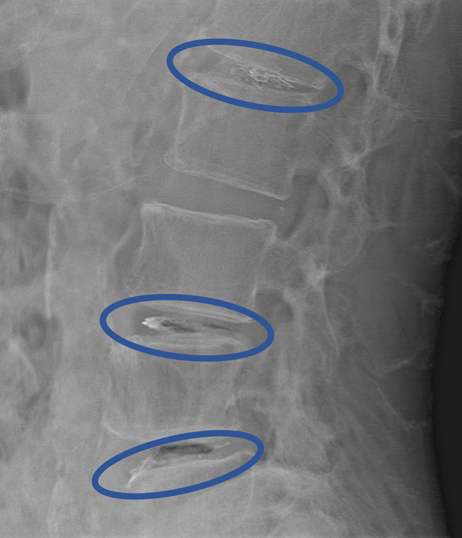

DiscoGelを入れた後の画像になります。

治療は 30分程度で終了

回復室で休憩後、歩いて帰院されました。